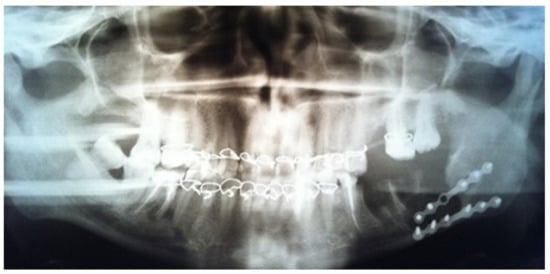

In the early postoperative period, a control panoramic view was made. The bone cavity, after extraction of the teeth and cystectomy, was visualized; titanium plates and screws were placed in the right positions. Additionally, the bone fragments were relocated into the correct position (Figure 4).

Figure 4.

Patient orthopantomogram 1 day after surgery.